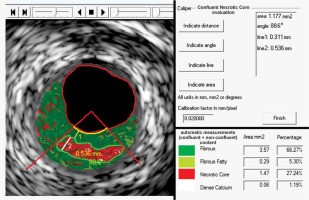

Figure 2

An illustrative example of fundamental importance of performing a matched-image (gray-scale IVUS/VH, A, and ChromaFlo, B) combined analysis to improve accuracy of the plaque luminal border delineation and ensuring same-spot analysis at baseline at follow-up. As the plaque luminal border may not be easy to determine (example in A), matched-image analysis, we introduced a routine application of a “matched image” analysis within the qVH algorithm [21]. This enables minimization of errors in plaque content quantification by VH analysis, that is critical for quantitative evaluation of the plaque composition, and in particular for the qVH measurement of fibrous cap thickness, cf. Figures 1 and 3). “Matched image” analysis plays also an important role in a longitudinal study of plaque evolution that requires a plaque image capture in the same spot (note side branch, SB, as a landmark, to minimize the likelihood of erroneous detection of a change in plaque characteristics as a result of a change in the sampling site along the arterial lumen) [28]